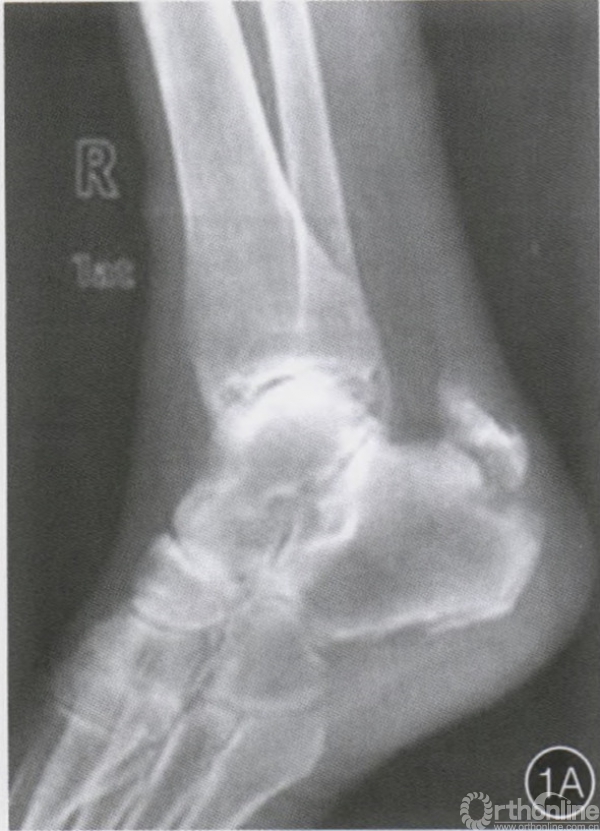

查体:右足跟部明显肿胀,皮肤瘀青,局部压痛明显;右踝关节主动跖屈及背屈活动明显受限。x线片示右跟骨结节骨折,

合并跟腱止点撕脱骨折,Beavis I型(图1A,B)。患者有原发性高血压病及糖尿病史,口服药物治疗,合并有老年性骨质疏

术前X片和示意图示右侧跟骨撕脱(A,B)